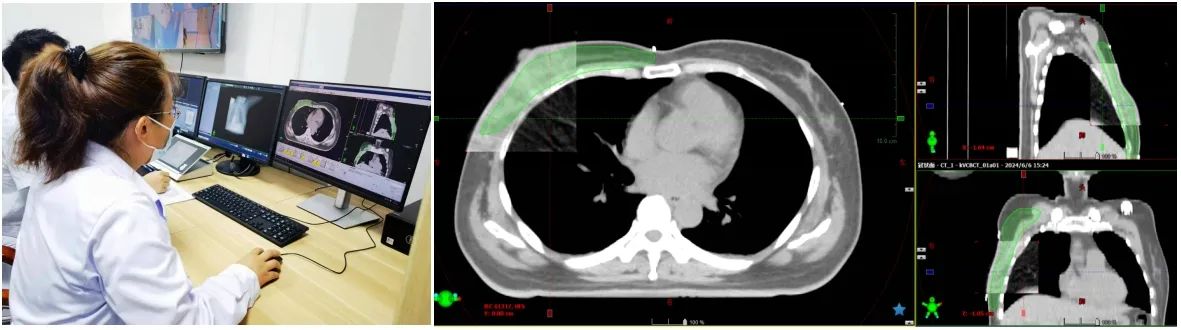

放射治疗的核心就是将加速器剂量准确投照到病灶(靶区)上,确保治疗位置的准确性是治疗工作的重中之重。在摆位工作的基础上,应用加速器的影像设备来确定靶区位置。如CBCT扫描,这是在治疗时获取如CT扫描一样的患者图像信息,通过与定位时的图像信息比对,获取患者位置误差,并进行在线校正,以此确保射线投照的精确性。

医生和物理师根据患者病情制定个体化的放疗计划,计划涵盖了静态调强、动态调强和容积旋转调强等放疗技术,每一种放疗技术治疗时间不一样、同一种放疗技术因射野参数不同,治疗时间也各异。另外,每周应用加速器的影像设备做位置验证时,患者在机房的时间也会有所延长,所以不同患者之间的治疗时长都不一样。